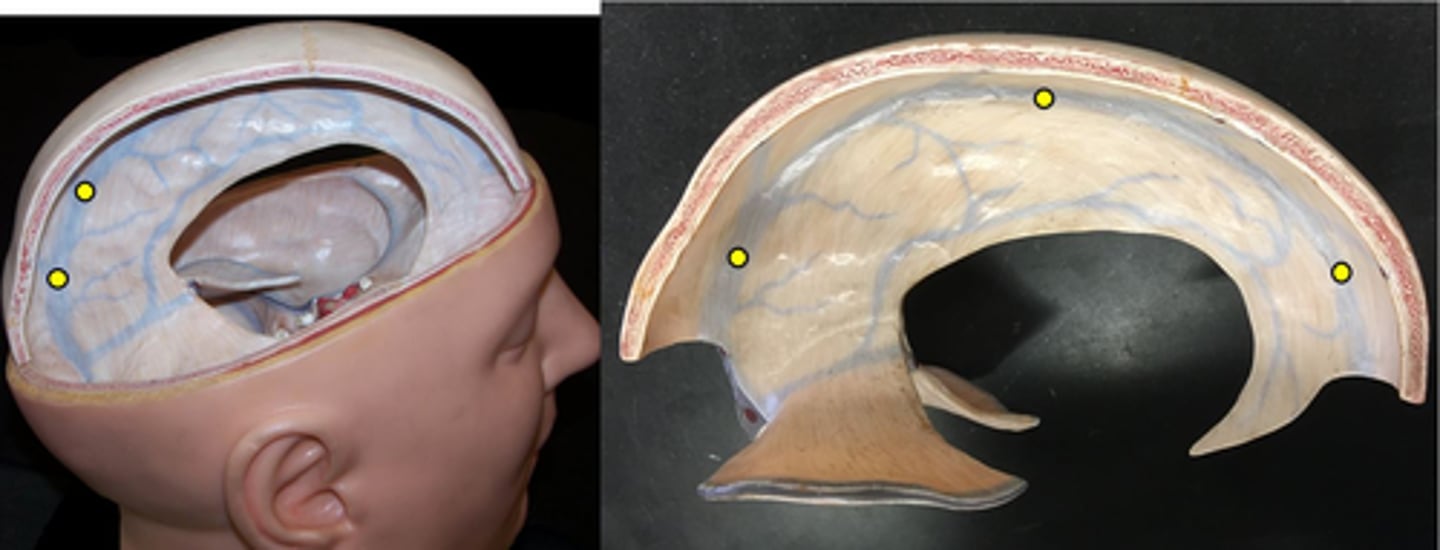

Dura mater

Number 3 on picture

Arachnoid mater

Number 2 on picture

Pia mater

Number 1 on picture

Falx cerebri

separates the two cerebral hemispheres

Tentorium cerebelli

separates cerebrum from cerebellum

Falx cerebelli

separates the two hemispheres of the cerebellum

Superior sagittal sinus

Inferior sagittal sinus

Transverse sinus